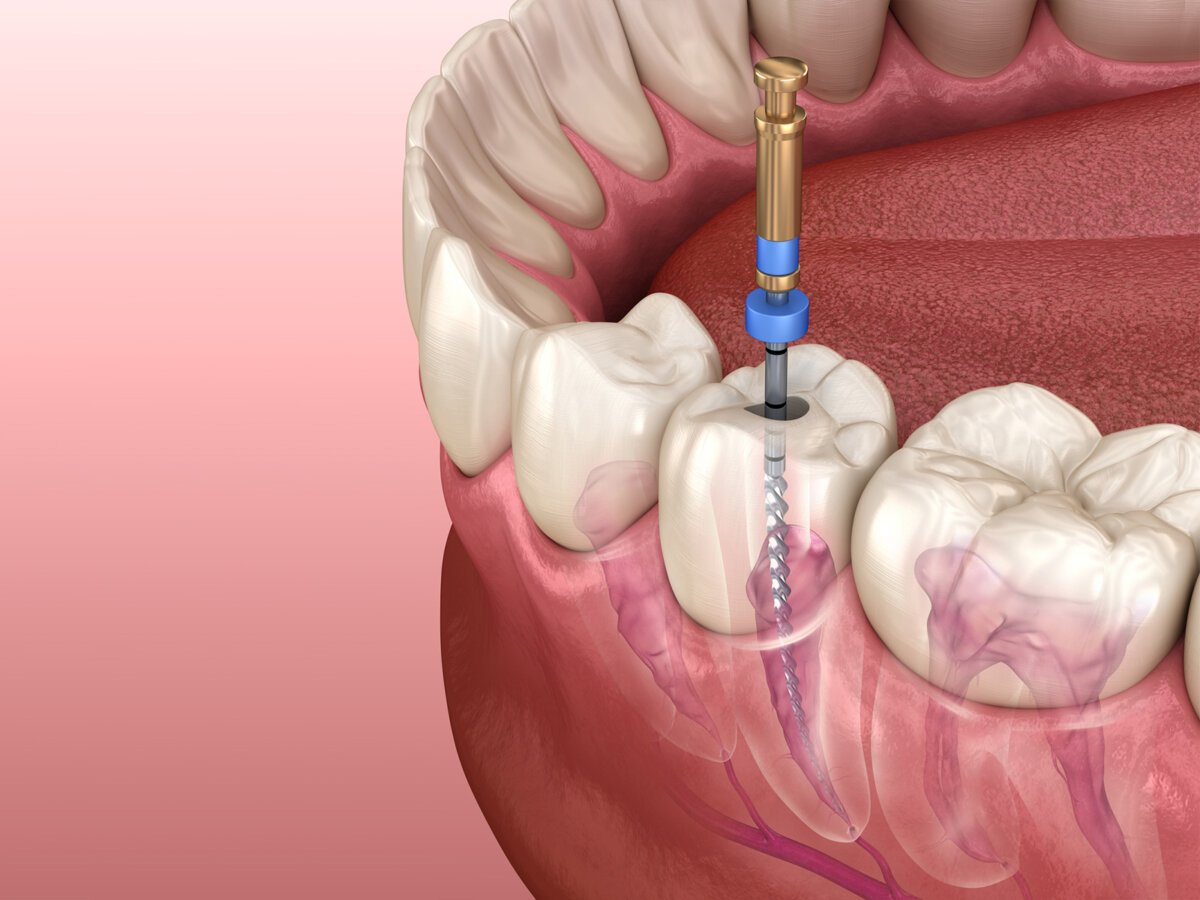

We visited sure cure dental clinic for my mother in laws treatment. We overall had very pleasant and comfortable experience. Dr akshay did a great job with root canal treatment and cap over that and also with implant, which was so comfortable and painless. We were anxious about treatment before going there. But we had it going so smooth.

I got my root canal treated by Dr akshay vala. It was really pain less. And my parents got their implats done at sure cure dental clinic by Dr akahay. And now they are also very satisfied. Thank you sir.